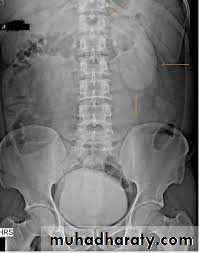

4. Full length film after release of compression .

5. A full bladder film (with the urinary bladder fully distended with contrast)

6. Post voiding full length film